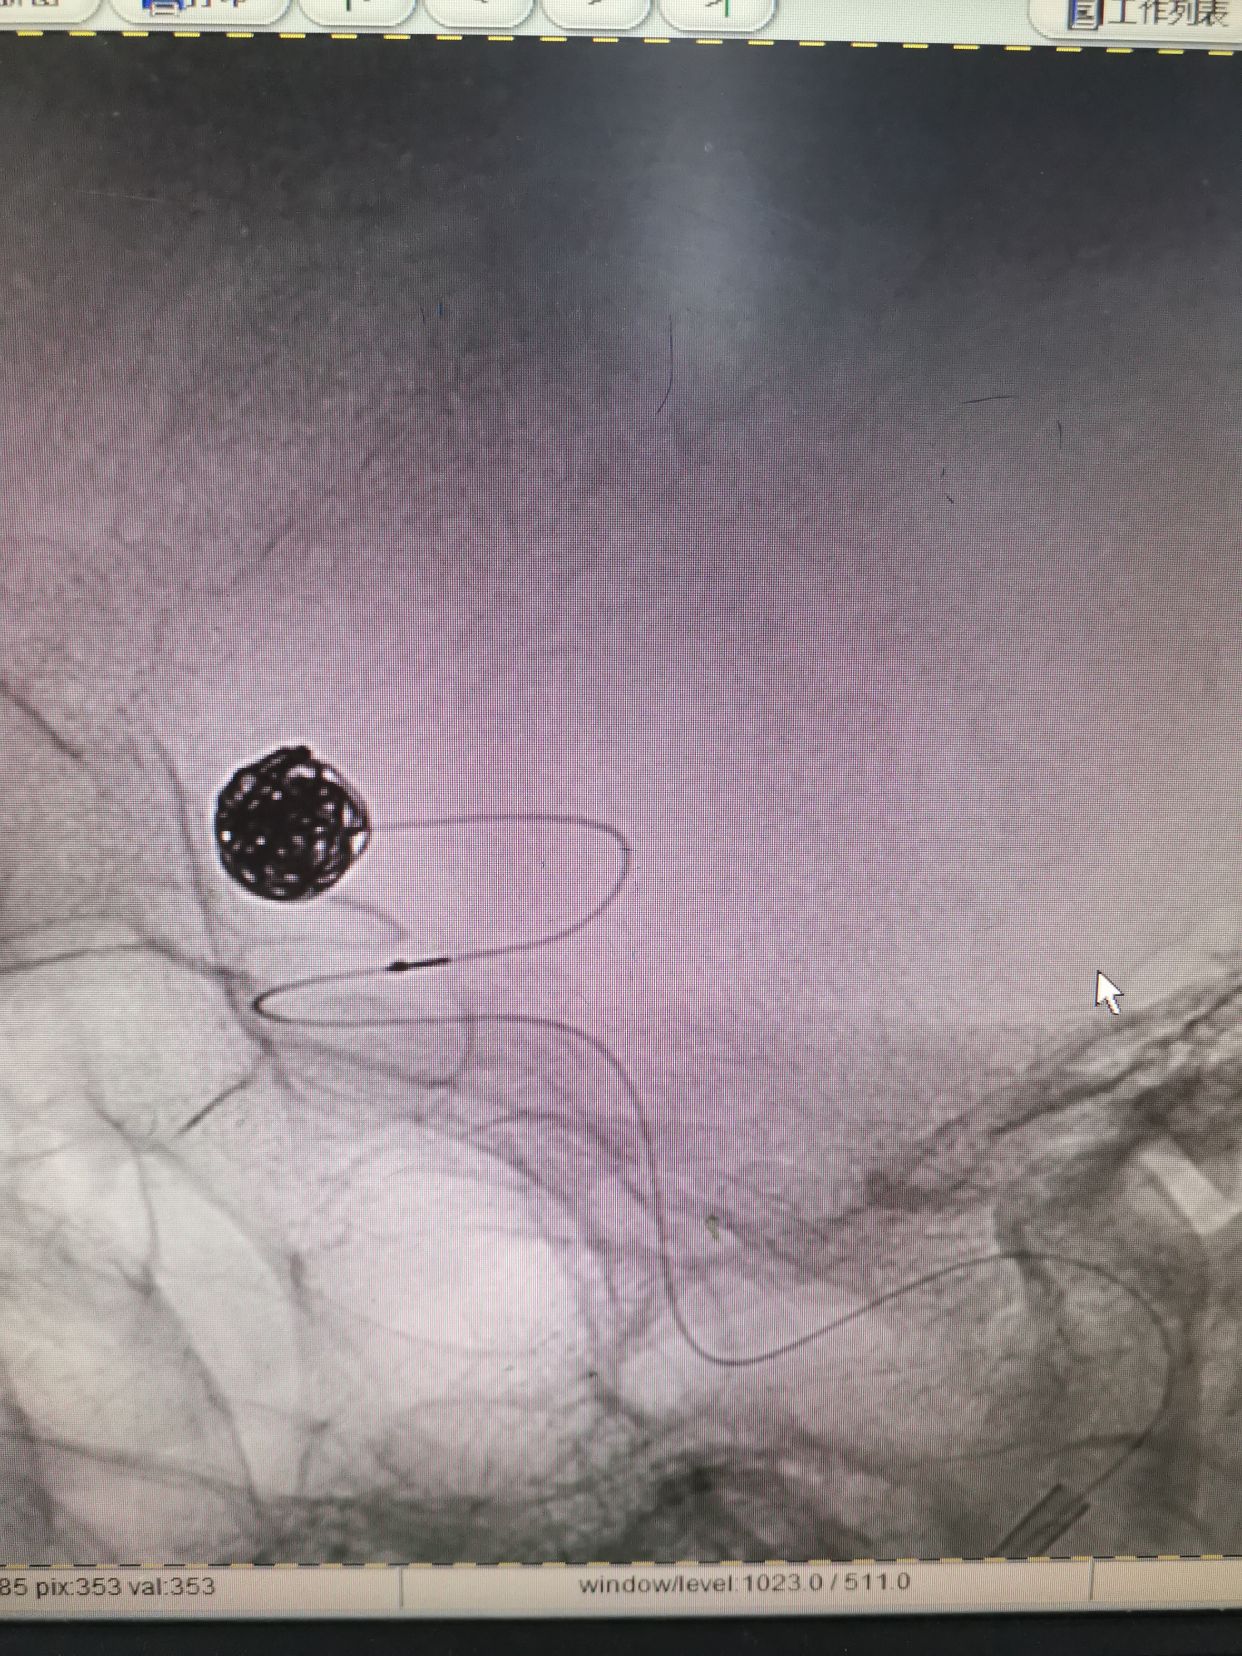

微导管到位后,填入Cosmos Complex 7mm/22cm

继续填入Complex 6mm/26cm

继续填入Complex 6mm/18cm

继续填入Complex 5mm/15cm